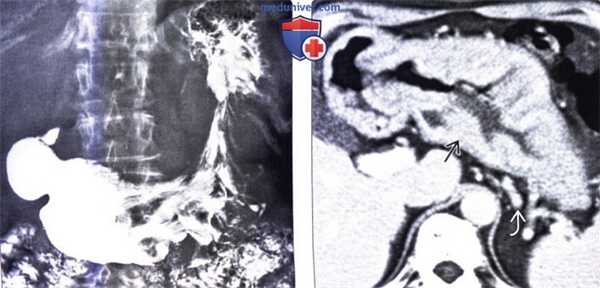

(Слева) На рентгенограмме, полученной при рентгеноскопии верхних отделов ЖКТ, определяется выраженное утолщение складок дна и тела желудка, практически не выраженное в антральном отделе. Обратите внимание, что бариевая взвесь плохо покрывает слизистую оболочку желудка из-за избыточной продукции муцина железами.

(Справа) На КТ с контрастным усилением у этого же пациента определяется значительное утолщение слизистой оболочки и подслизистой основы, однако признаков распространения процесса в околожелудочные ткани нет. Артериальные и венозные сосуды полнокровны, что обусловливает гиперемию желудка.